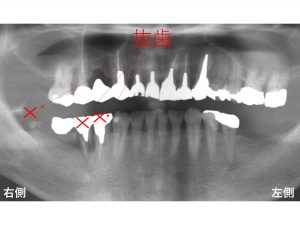

治療前です。

下顎右側の奥歯が取れたとのことで来院されました。

奥歯の3歯は、歯根破折していました。

残念ながら抜歯しか方法はありませんでした。

以下のような治療プランをご説明させていだきました。

抜歯後の3歯欠損に対して、

2本のインプラントを埋入し、3歯分の被せ物を作成するインプラントブリッジです。

このような治療法が一般的に行われます。

しかし、患者様は歯根破折はしているが、

一番手前の歯は抜歯を避けたいとの強いご希望がありました。

最終的には以下のようなプランとなりました。

まず奥の2歯のみ抜歯します。

手前側の歯は抜歯しないわけですから

患者様が気にしていた見た目は少しでも軽減できます。

また抜歯しないわけですからこの部分では噛めます。